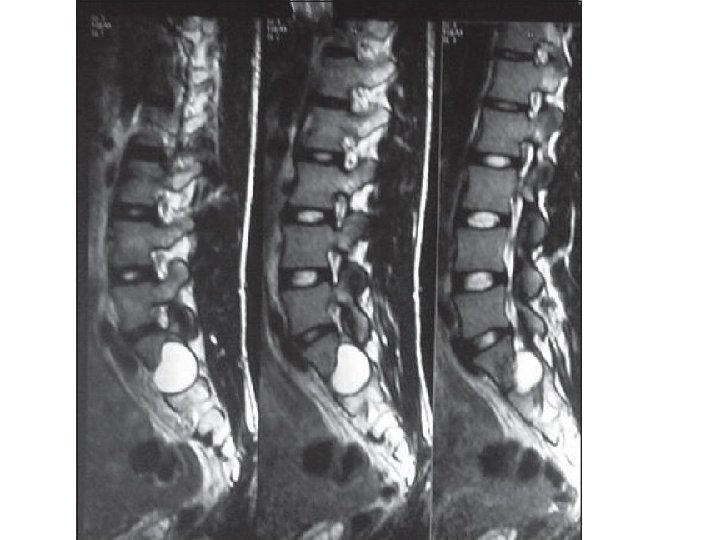

CYSTIC HYDATID DISEASE OF THE SPINE • The surgical approach to patients with spinal hydatid disease usually includes a combination of : • decompressive laminectomy, • removal of cysts. • excision of involved bone. • stabilization of the spine.

• Almost 50% of these lesions may rupture during surgery because of the narrow space in which the surgeon has to work. • involvement of adjacent bone and multiplicity of lesions make complete removal of spinal cysts difficult. • Hydatid disease recurs after surgery in up to 40% of patients, and this complication is associated with neurological deterioration. • albendazole is advised to reduce such complications.